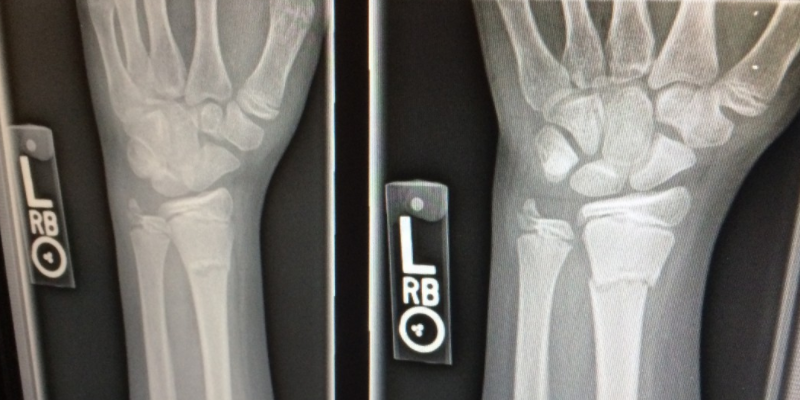

특히 골절 등 뼈가 부러지거나 상처를 입었을 때에 빠르게 회복 할 수 있도록 도와 주어 뼈가 생성되는 과정에 기여하여 보다 튼튼하고 밀도가 높은 뼈를 만들 수 있도록 해 주는데요. 때문에 노령층 뿐만 아니라 성장기 아이들에게도 꼭 필요 한 영양 성분이라고 합니다.